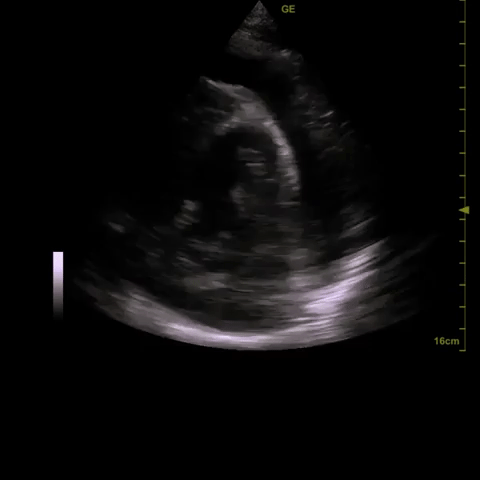

2) ?pericardial effusion (small one noted on initial CT scan)

A diagnostic echocardiogram was performed which was consistent with the POCUS findings. In discussion with Cardiology, a percardiocentesis was performed and over 1L of fluid was aspirated from the pericardial sac (good access from the A4C window). The patient tolerated this well and had a very modest increase in blood pressure following the procedure.

- There are several echocardiographic signs of increased intrapericardial pressure: RA collapse, RV diastolic collapse, and increased mitral/tricuspid inflow variation